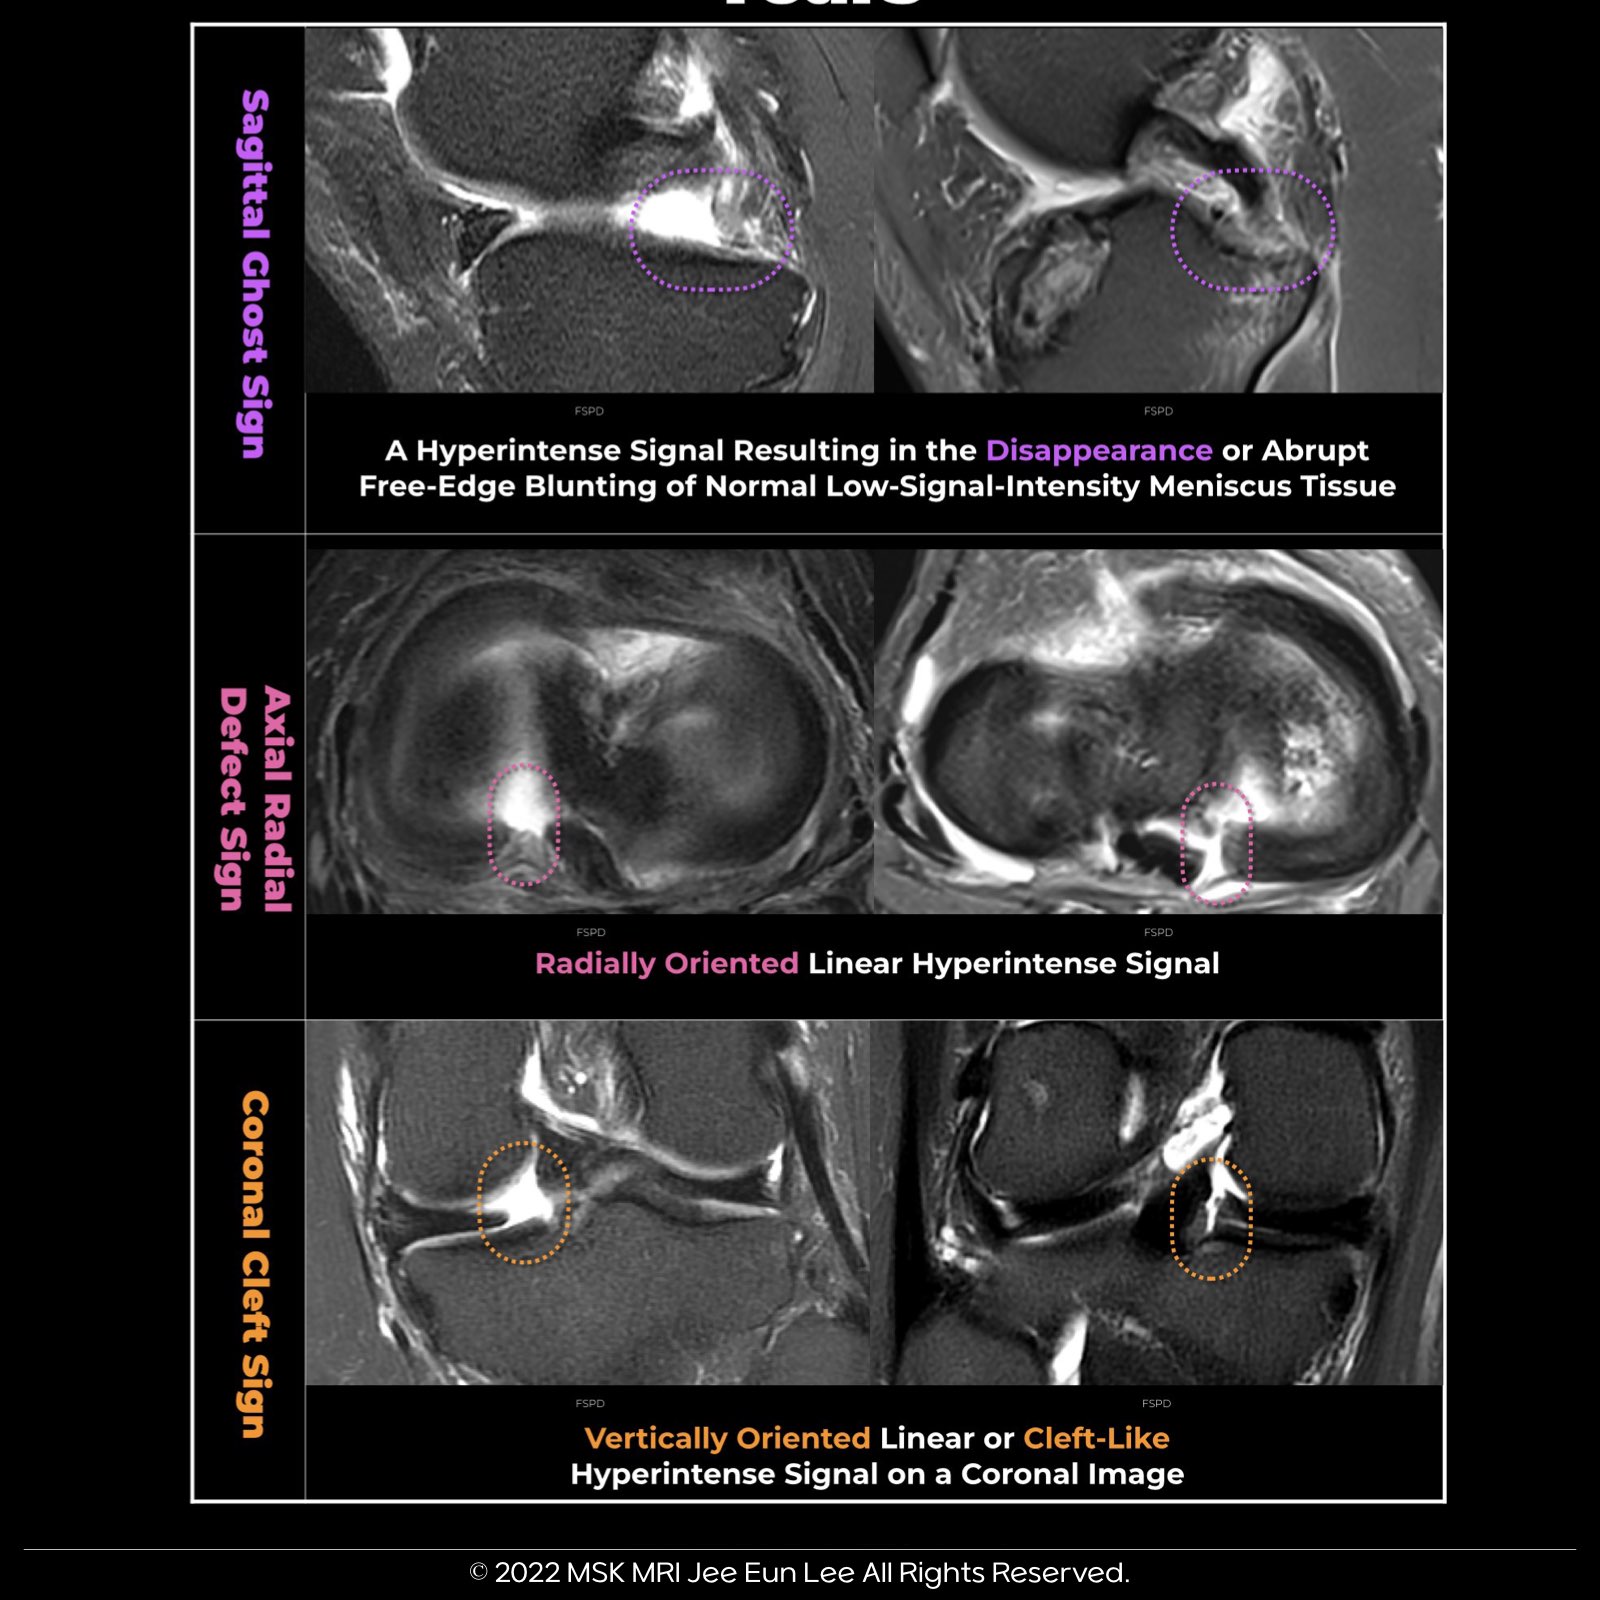

Among the primary MRI signs of root tears, three commonly used findings are:

Sagittal Ghost Sign:

- This sign is characterized by a hyperintense white signal intensity that leads to the disappearance or abrupt blunting of the normal low-signal-intensity meniscus tissue.

- It is typically observed on a sagittal image.

Axial Radial Defect Sign:

- The axial radial defect sign presents as a linear, radially oriented hyperintense signal on an axial image.

Coronal Cleft Sign:

- The coronal cleft sign manifests as a vertically oriented linear or cleft-like hyperintense signal on a coronal image.